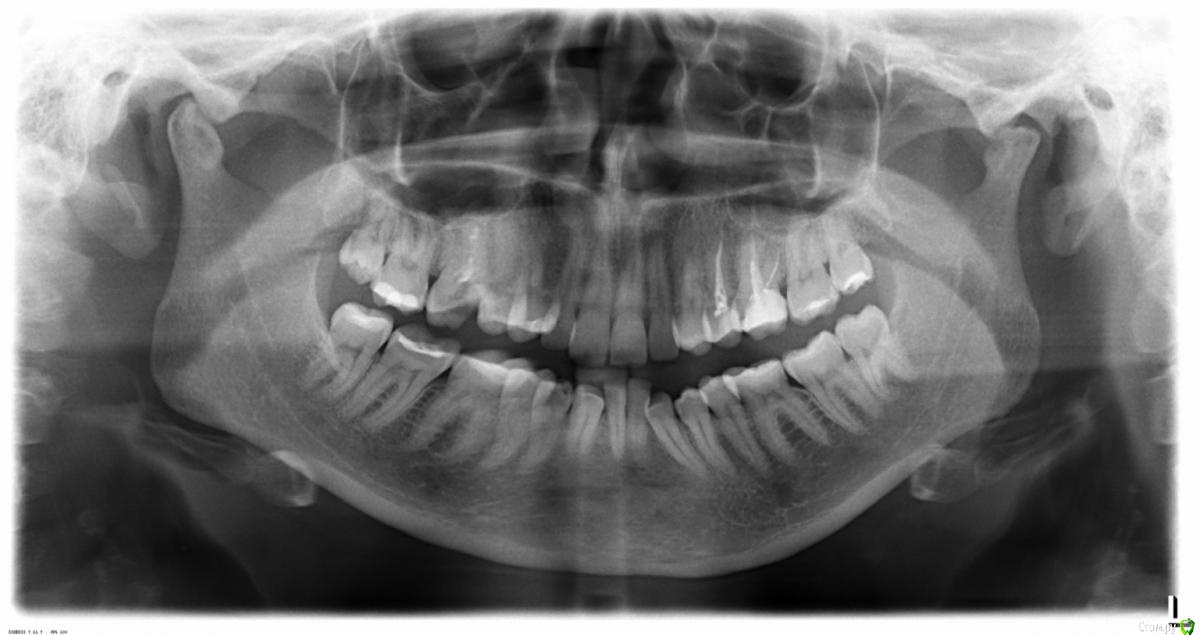

strator Опубликовано 23 апреля, 2015 Поделиться Опубликовано 23 апреля, 2015 Добрый день, откололась часть зуба - правый верхний, если считать с центра на снимке - 5 по счету (сейчас стоит временная пломба). сказали, что на нем киста.подскажите, пожалуйста, действительно ли это так и большая ли она. и действительно ли его надо обязательно удалять как можно быстрее. если да, то могут ли быть проблемы с имплантацией потому что есть киста.и можно просто запломбировать зуб и жить с кистой дальше? Ссылка на комментарий

Scrabble Опубликовано 23 апреля, 2015 Поделиться Опубликовано 23 апреля, 2015 Этот снимок совершенно не информативен-сделайте прицельный. Ссылка на комментарий

Гарриевич Опубликовано 23 апреля, 2015 Поделиться Опубликовано 23 апреля, 2015 и можно просто запломбировать зуб и жить с кистой дальше? если зуб хорошо пролечить, то "киста" исчезнет в Вашем случае, нужен прицельный снимок интересующего зуба, на этом ОПТГ не видно 1 Ссылка на комментарий

red_butler Опубликовано 24 апреля, 2015 Поделиться Опубликовано 24 апреля, 2015 кисты не вижу, но проблем хватает. Делайте прицельные снимки или Кт 1 Ссылка на комментарий